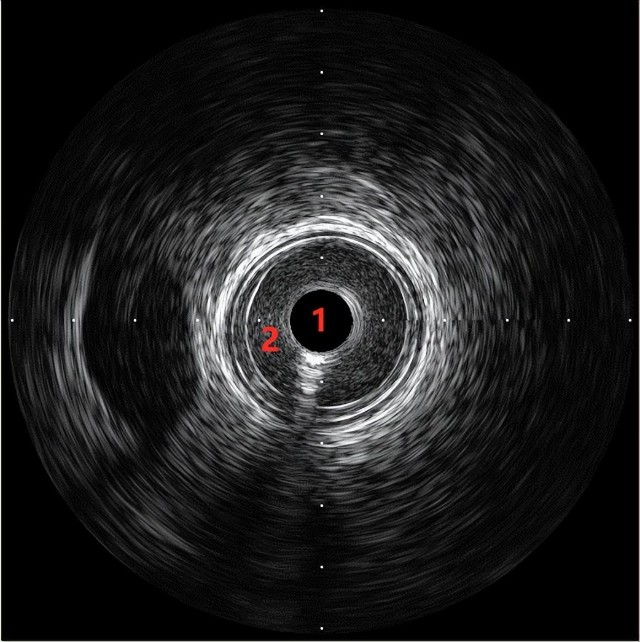

冠状动脉的血管壁由具有不同回声特性的层状结构组成,在IVUS上可呈现3层结构,即内层代表内膜和内弹力膜,表现为纤薄的白色回声带;中层为中间无回声层(黑色或暗灰色),代表中膜;外层有特征性的“洋葱皮”样表现,代表外膜和外膜周围的组织。而血管的外膜边界通常无法识别,主要是由于外膜和周围组织无明显的回声差异。

图为冠状动脉的血管内超声图像,1为导管,2为管腔。